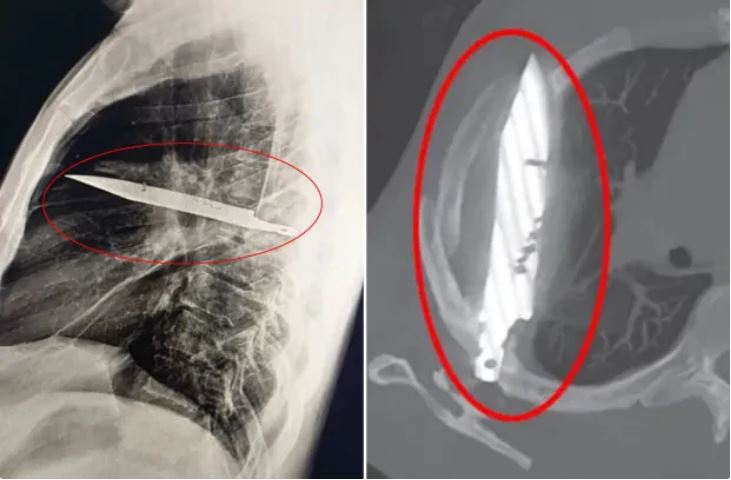

८ वर्षसम्म छातीमा अड्किएको चक्कु, अहिले मात्र खुल्यो रहस्य

सोमबार, भदौ २, २०८२